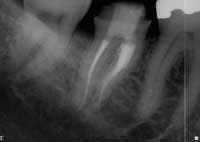

Coronal seal

The vital importance of coronal seal in endodontics cannot be overstated. Gutta percha exposed to saliva for any appreciable period of time is contaminated with bacteria and should be retreated. Clinically, the use of a bonded obturation material, such as Resilon (Resilon Research, Madison, Conn.) or RealSeal (SybronEndo, Orange, Calif.) can help significantly diminish coronal microleakage. In addition, and more importantly, the placement of a bonded core buildup as soon as possible after completion of the root canal can help guard against this preventable clinical failure (Fig. 3).